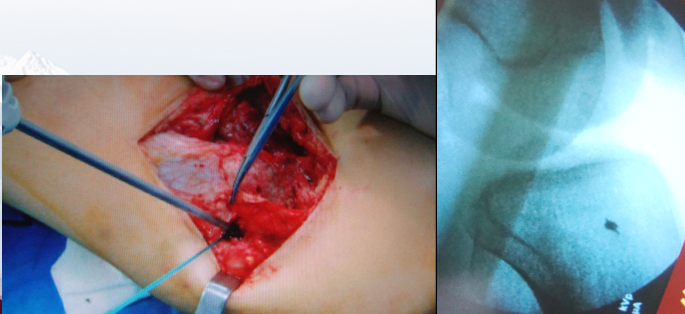

2.带线锚钉治疗交叉韧带下止点骨折

前交叉韧带(anterior cruciate ligament,ACL)胫骨止点撕脱骨折实际上是一种特殊类型的ACL损伤,应早期修复,避免交叉韧带重建。

传统法:传统手术治疗膝关节交叉韧带下止点骨折的方法有克氏针张力带法、钢丝法、丝线法、加压螺钉法等,但都存在一定的不足。克氏针张力带法固定欠牢靠;钢丝法、丝线法都需要在胫骨上钻制两个左右的骨洞,较费时;加压螺钉法对于骨块较小及粉碎性骨折不适用。

带线锚钉法:适应证较广,不受骨折块大小的限制,不需要术中透视调整螺钉的方向,操作较为简单,手术时间也相应缩短。